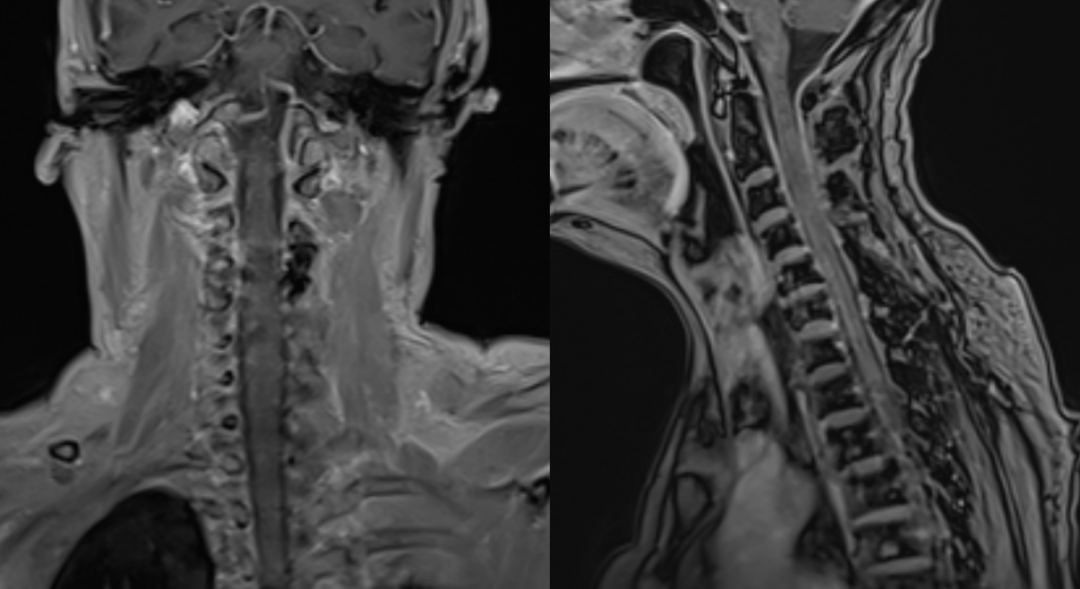

入院查脊髓MRI提示颈2-3椎管内占位,考虑为颈2-3椎管内脊膜瘤,完善相关检查后行颈椎管内肿瘤切除术。

术前磁共振图片:

术后磁共振:肿瘤完整切除